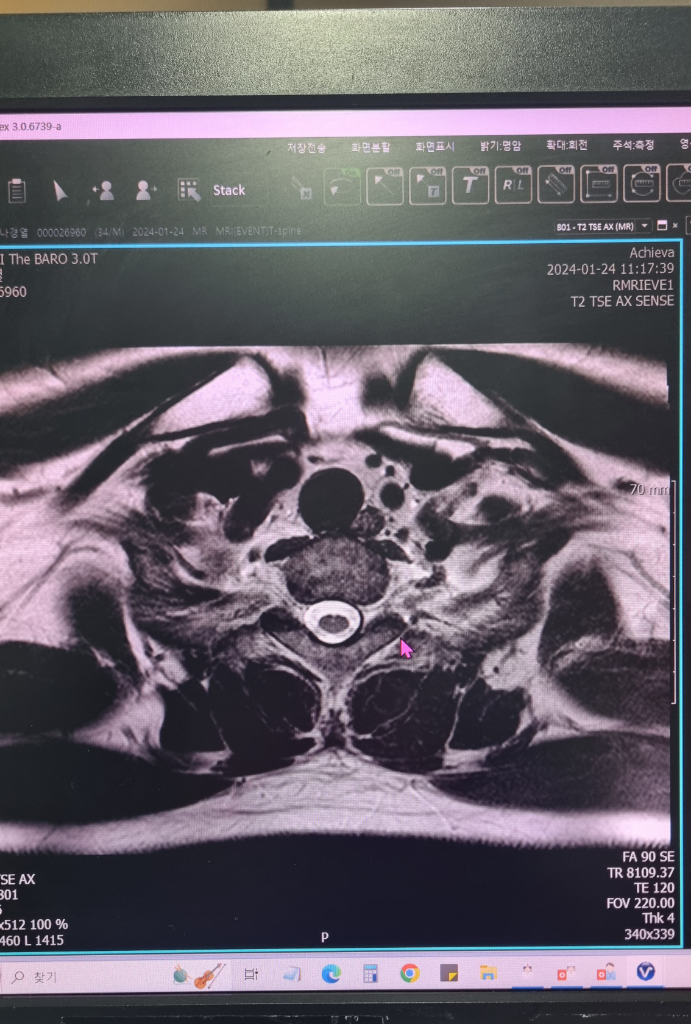

정확한 통증의 원인을 파악하시는게 맞겠습니다. MRI 에는 T1, T2 이런식으로 여러가지 영상이 들어있습니다.

지금 보여주시는 영상은 아마 T2 영상일거라고 생각됩니다. MRI로는 골절이 급성기 상태인지 이전에 있었던 골절인지를 감별할 수 있습니다.

아래 사진중에서 첫번째 사진이 T1 영상이고 두번째 사진이 T2 영상입니다. 보시는것과 같이 급성기 골절에서는 T1에서 검정색으로 보이고 T2에서는 하얀색으로 보이는 특징을 가지고 있습니다. 그런데 올려주신 사진 T2 에는 음영이 증가해있지 않습니다. 즉, 최근에 부러진게 아니고 이전에 부러졌는데 지나갔던 병변일 가능성이 높다는 의미입니다. 이런 경우는 주로 디스크 손상과 연관된 종판손상으로 생각할 수 있습니다.